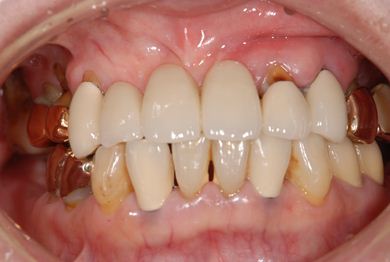

インプラントの症例写真 IMPLANT

| 性別/年齢 | 女性 / 58歳 | ||||||||||||||||||||||||||||||||

| 主訴 | インプラント治療を希望。 | ||||||||||||||||||||||||||||||||

| 治療内容 | インプラント8本(抜歯即日スピードインプラント、サイナスリフト)、ハイブリッドセラミック8本 | ||||||||||||||||||||||||||||||||

| 総治療費 | 3,495,050円 | ||||||||||||||||||||||||||||||||

| 治療期間 | 1年0ヶ月 |